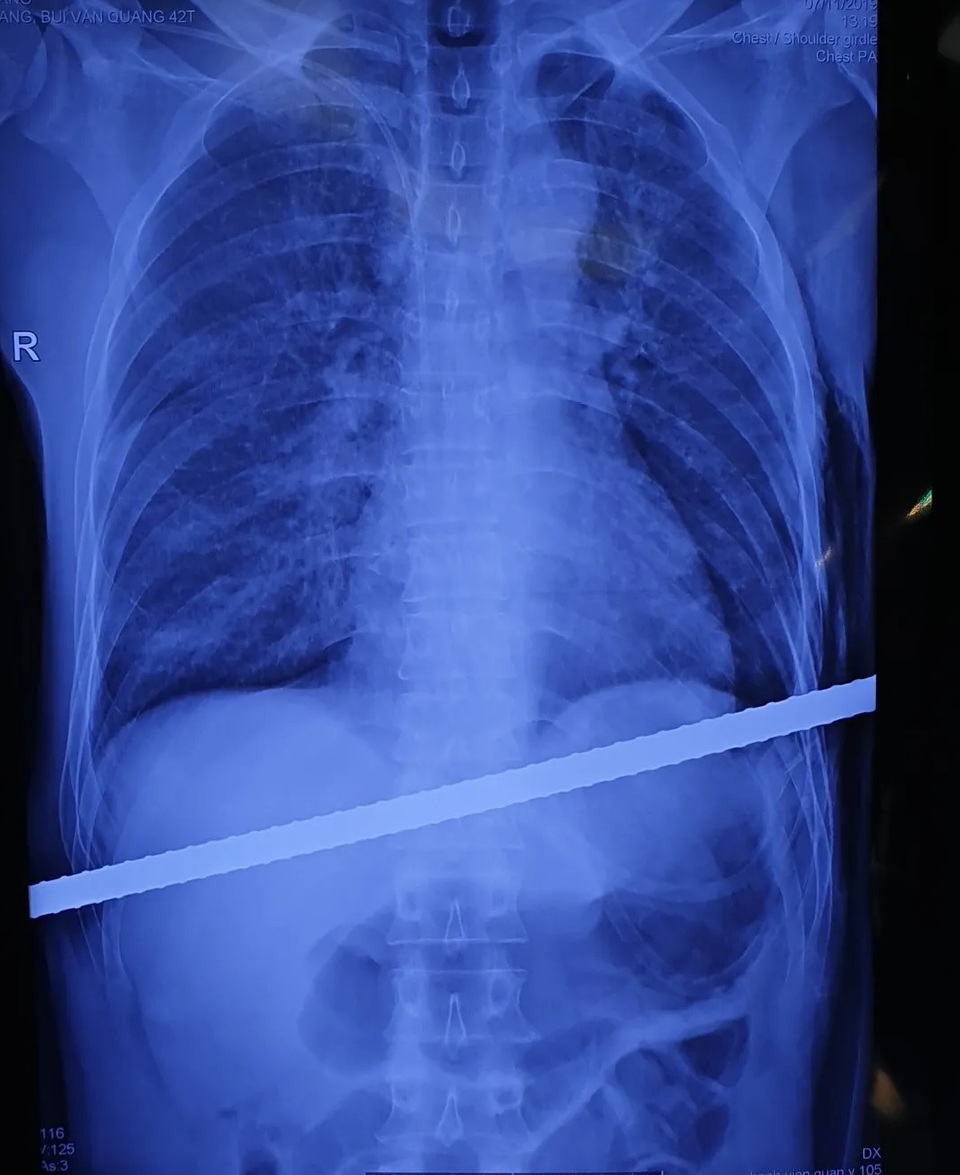

(Dân trí) - Không may bị ngã cầu thang do tai nạn lao động, nam bệnh nhân 42 tuổi bị thanh sắt đâm xuyên từ bờ dưới của sườn bên phải ngang qua người. Thanh sắt đâm xuyên qua gan, màng phổi bệnh nhân.

Ca tai nạn hi hữu được chuyển đến bệnh viện cấp cứu chiều 11/7, trong tình trạng bệnh nhân vẫn còn nguyên thanh sắt đâm xuyên qua người.